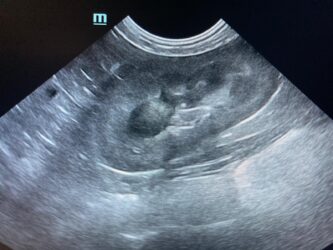

Dimitri, CV, 9.6kg, 11j, MC, bijgeruis 4/6 waarvoor hij vetmedin krijgt en opgevolgd wordt door cardioloog:

21/08/2025: Bij buurtcollega aangeboden voor hematurie. Plast vlot, op’t einde bloed te zien. Mevr. kookt zelf voor hem. Echo gehad + UOZ (geen idee hoe dit werd gecollecteerd) gedaan. Veel bloed in de…